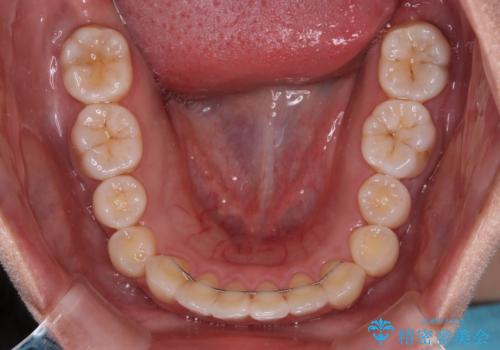

上下顎ともに歯列全体の後方移動とIPR(歯と歯の間を削る)によってデコボコが解消するように設計し、インビザラインにより治療を行うこととしました。

上下ともにIPRを積極的に行っているため、舌の突出癖をしっかりと改善できないと、後戻りにより隙間やデコボコが早い段階で発現することになるため、舌のトレーニングが非常に大切になります。